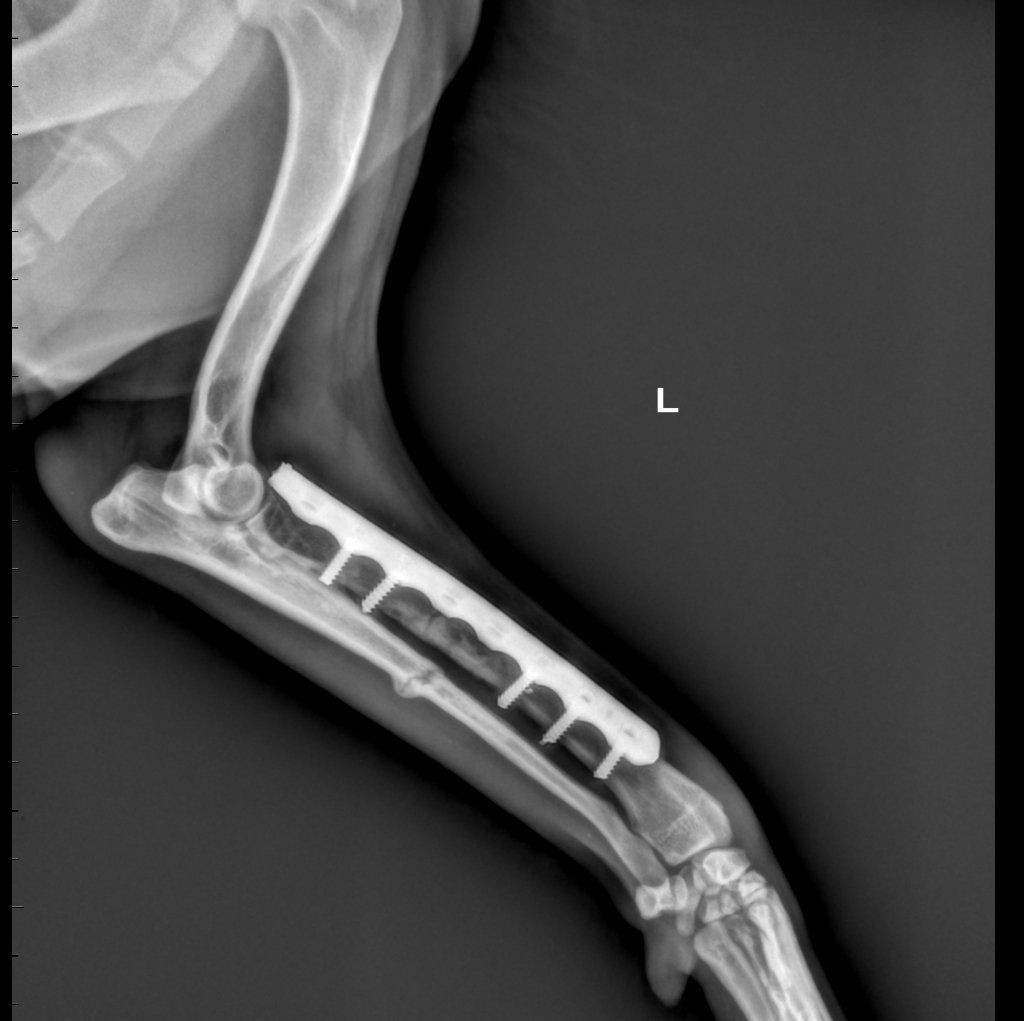

Diagnostica per immagini

Tra i servizi che l’Ospedale Veterinario Città di Conegliano fornisce, non mancano quelli di diagnostica per immagini:

ecografia, radiologia digitale, TC.

Gli specialisti Roberto De Pellegrin e Riccardo Pelizzon, in particolare, si occupano degli esami ecografici, ecocardiografici, tomografici per l'acquisizione di immagini del corpo del paziente attraverso l'esposizione a ultrasuoni o a raggi X.

Si tratta di esami non invasivi né dolorosi, che possono essere eseguiti molto rapidamente.